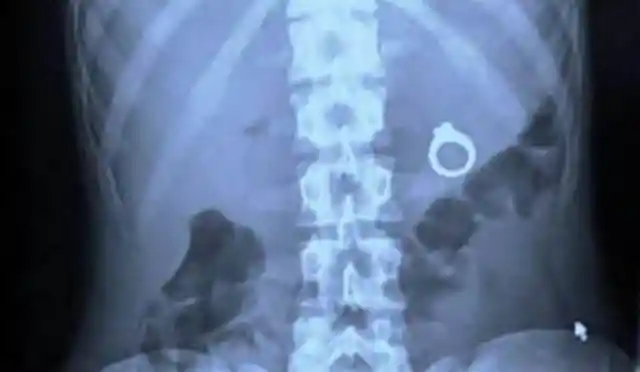

If You Like It, Don’t Put A Ring In It

When planning the perfect wedding proposal it is fair game to take risks to make a good impression, but how far would you be willing to take it? In this case, a man in New Mexico went for a rather romantic setting—a wholesome diner—where he decided to pop the question by putting an engagement ring inside her drink.

Unfortunately, it didn’t go quite as planned, and the bride-to-be chugged her beverage a little too hard. After a rush to the emergency room and getting an X-ray, they found the ring on its way to her stomach. We hope the answer was yes, and whether it was while the ring was inside her or on her finger, it's still a fabulous—if not embarrassing—engagement story.